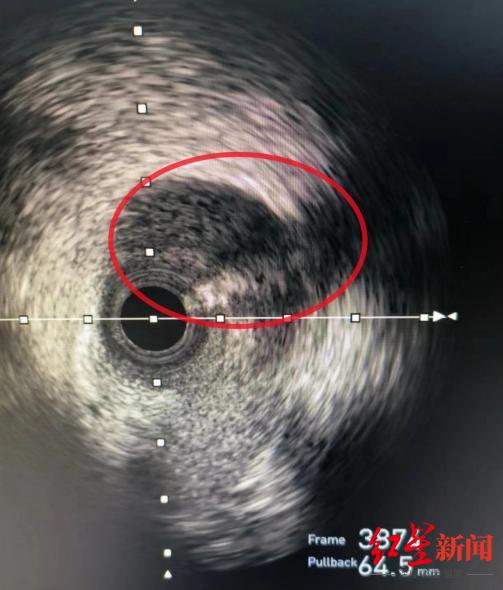

血管表现出“断层式的狭窄”,这不是常规的动脉粥样硬化疾病表现。在迅速判断后,心血管内科胸痛急诊团队又为王女士开展了腔内影像学IVUS(冠状动脉血管内超声)进一步检查并精准找到了病因——前降支血管夹层影像,俗称自发性冠脉动脉夹层(SCAD)。简单来说,就是血管内壁有撕裂,漏出的血液被尚还完好的血管外壁兜着,犹如自行车胎“鼓包”。

通过冠状动脉血管内超声检查,医生找到了王女士血管夹层破口的位置,并对血肿对管腔的压迫情况及残存管腔情况进行了判断。夏茏介绍说,自发性冠状动脉夹层是一种较为罕见的心血管疾病,可因形成的血肿压迫血管引发心梗,其死亡率却高达为70-75%,“好在夹层破口撕裂到中远端就停止了,血肿未完全压迫血管,心梗的程度较轻微。”基于完善的检查结果和综合判断,目前暂时可以不作介入支架治疗干预,待自身血肿慢慢吸收和夹层逐渐愈合。不过,需要同步接受密切观察,警惕血管问题进一步加重。